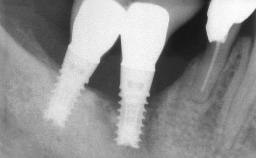

Peri-implant Carcinoma

Oral implants are highly successful and offer long-term benefits, especially in the rehabilitation of edentulous patients or patients with oral defects following ablative tumor surgery (Albrektsson and coworkers 1986), and also after radiation therapy (Schiegnitz and coworkers 2014). With the number of implants placed globally going into the millions, implant dentists have observed some rare adverse events. Although carcinogenesis around implants is an exceedingly rare phenomenon, we recently reported about 15 patients treated for carcinomas adjacent to implants at our clinical department over a period of fifteen years (Moergel and coworkers 2014). The following case represents a patient of this cohort; it discusses possible risk factors and makes suggestions for a recall schedule. A 70-year-old woman was referred to our outpatient department for evaluation of a rapidly growing macroscopic alteration of the mucosa in the left mandible.

# of Implants 4

Type of Implants One-Piece